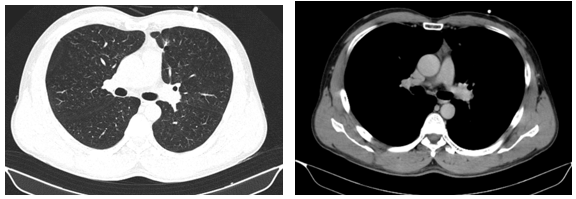

-         Chụp cắt lớp vi tính lồng ngực: phim trước điều trị

Hình 1. Trên phim chụp CT lồng ngực ở cửa sổ nhu mô: thùy trên phổi trái có khối đặc tròn bờ tua gai, kích thước: 29 x20mm, kính mờ và dày kẽ xung quanh, lân cận có nốt bán đặc kích thước 29 x 17mm, ngấm thuốc không đồng nhất sau tiêm, nghi ngờ có phần xâm lấn trung thất trước. Nhu mô thùy còn lại và nhu mô phổi phải lan tỏa các nốt đặc tròn to nhỏ không đều, đường kính: 2-8mm.

-         Cắt lớp vi tính lồng ngực:

Sau 3 tháng điều trị đích:

U nguyên phát và u thứ phát ở cả 2 phổi đều giảm kích thước rất nhiều, không thấy hạch trung thất.

Sau 6 tháng điều trị:

U nguyên phát chỉ còn kích thước rất nhỏ, u thứ phát 2 bên phổi đã mất hết.